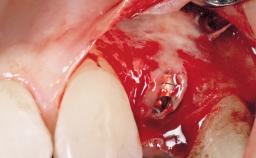

A 56-year-old female patient was referred to the clinic for the functional rehabilitation of her left mandible. The healthy, non-smoking patient presented with loss of retention of crown 35 due to secondary root caries. In addition, she had a single-tooth gap at site 36 with clearly discernible facial atrophy. The panoramic radiograph exhibited crowned teeth 35 and 37, both with a root canal filling. Tooth 37 showed a radiolucent area on the mesial aspect. Tooth 38 did not show any signs of pathology. Based on the clinical and radiographic findings, it was decided to remove root 35 and tooth 37, creating an extended edentulous space with three missing teeth. As requested by the patient, tooth 38 was left in place. The removal of both teeth was done without major flap elevation. The wound margins at site 35 had to be slightly elevated to remove the root remnant.